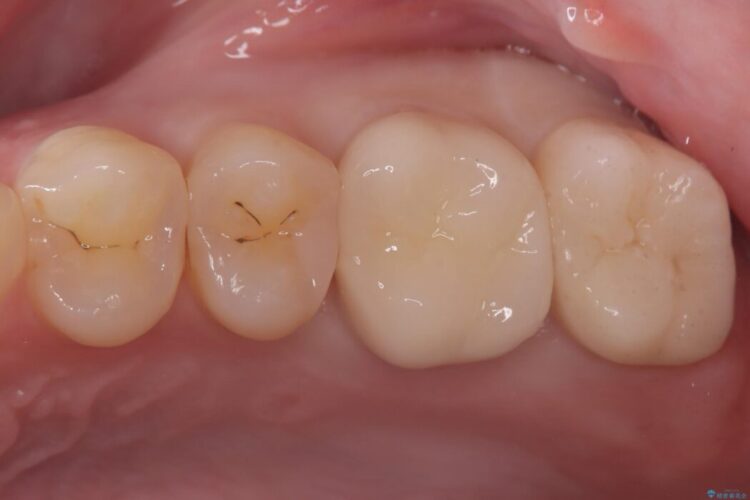

欠けた奥歯をPGAで補強。違和感のない咬み心地へ

欠けた奥歯をPGAで補強。違和感のない咬み心地へ ビフォー 欠けた奥歯をPGAで補強。違和感のない咬み心地へ アフター

以前治療した奥歯(右下7番)の詰め物が欠けてしまったとご来院された患者様です。